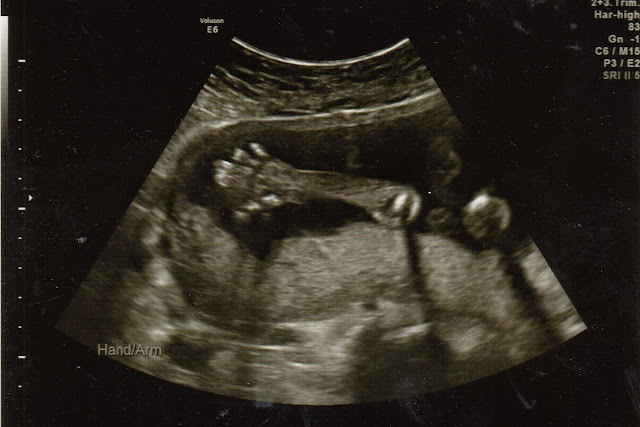

Finally, we got to meet the little kung fu champ:

Isn't she cute??? I think she's rubbing her eye in that profile shot. And, yes, we have mostly definitive proof our little kung fu champ is a she: